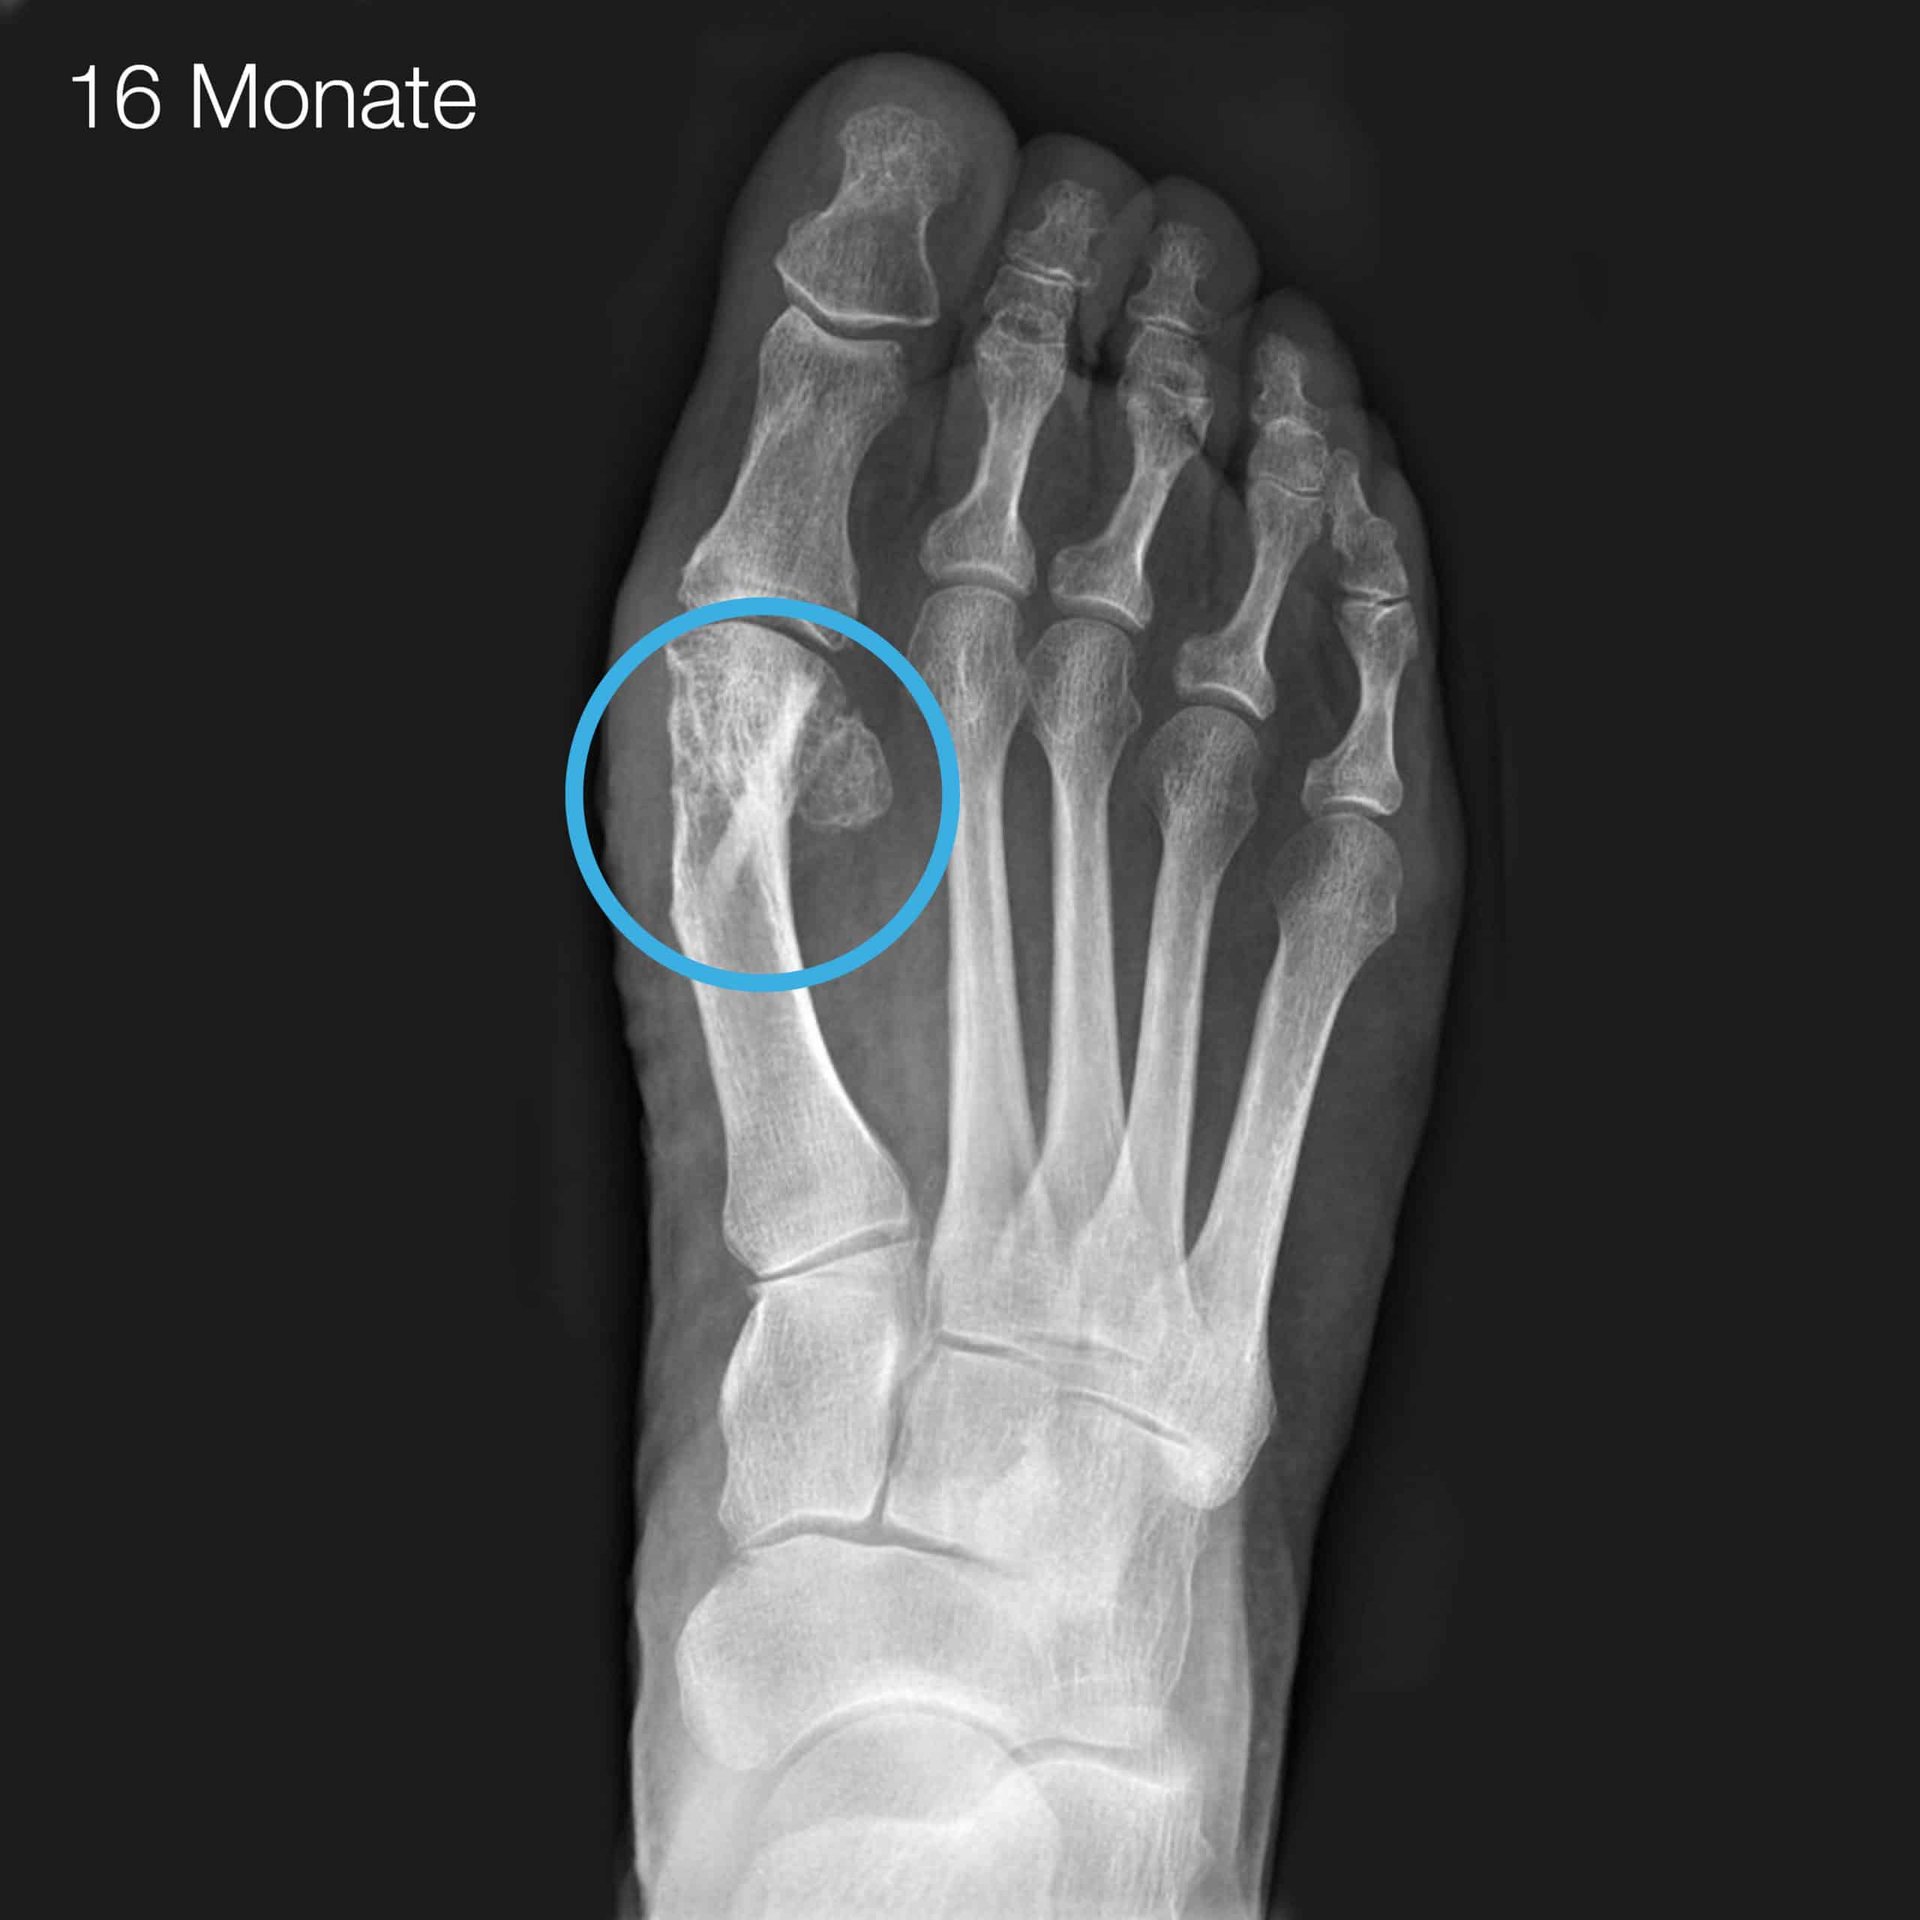

1 I. Brcic, K. Pastl, H. Plank, J. Igrec, J. E. Schanda, E. Pastl, M. Werner. Incorporation of an Allogenic Cortical Bone Graft Following Arthrodesis of the First Metatarsophalangeal Joint in a Patient with Hallux Rigidus Life (2021)